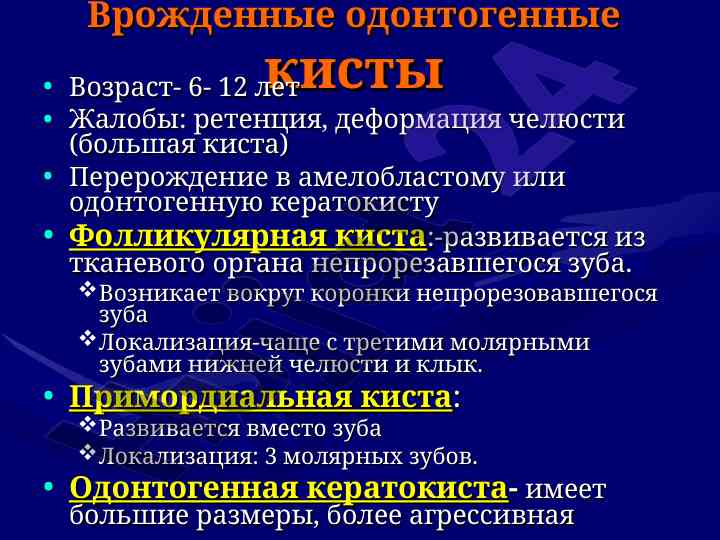

Данная лекция охватывает диагностические критерии, локализацию и структуру кист и опухолей челюстно-лицевой области, включая одонтогенные и неодонтогенные кисты.